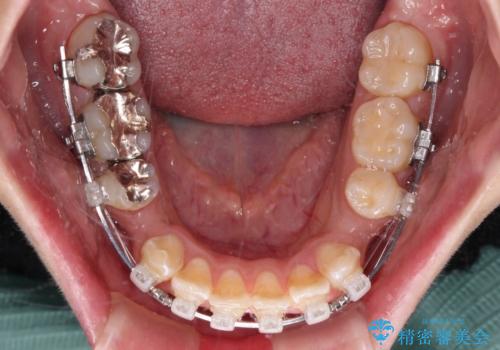

- クリアブラケット

- 前歯のクロスバイトと、口元が閉じにくいとのことで来院された患者様です。

口元の突出感を改善する必要があるため、上下左右の第1小臼歯4本を抜歯し、ワイヤー装置にて矯正治療を行うこととしました。

むし歯のリスクが高かったため、治療が長期化しないように心がけました。

当初の予定通り、2年強で無事に治療を終えることができました。